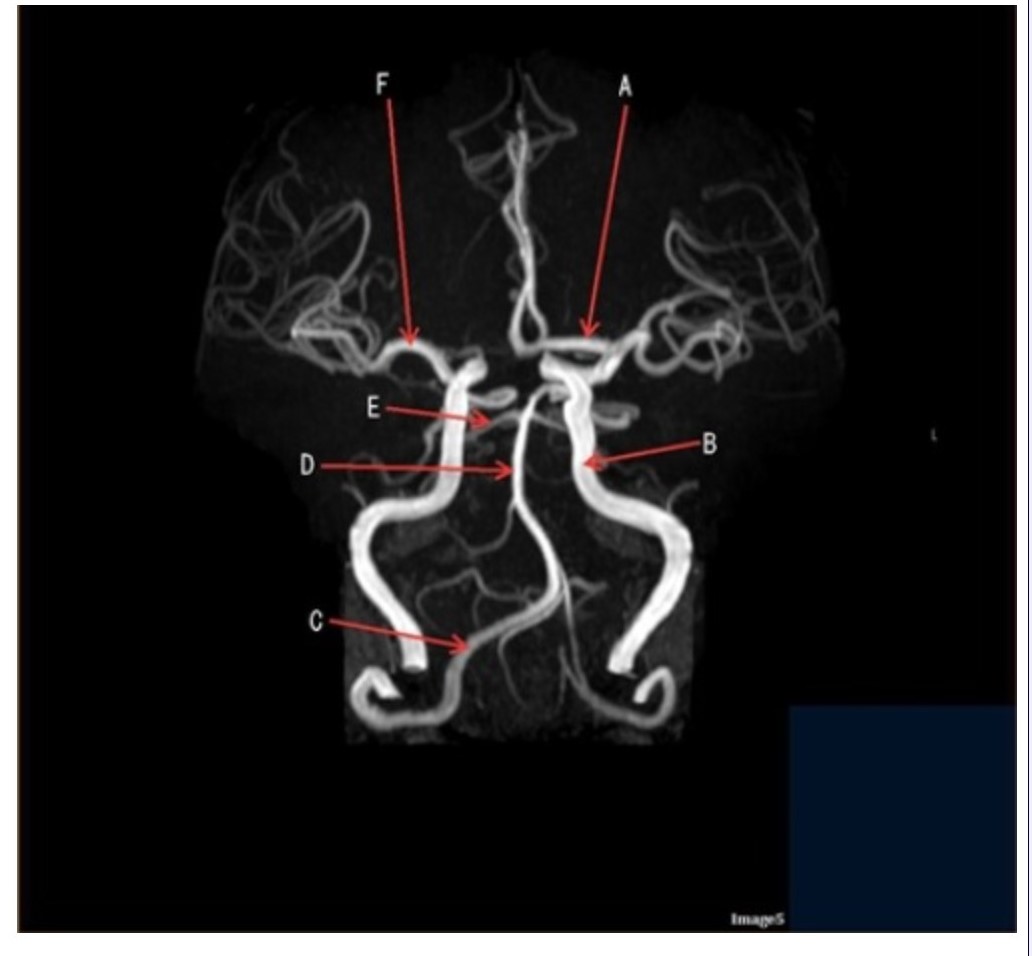

Letter D in Image 5 is pointing to:

A. Anterior cerebral artery

B. Internal carotid artery

C. Basilar artery

D. Posterior cerebral artery

E. Middle cerebral artery

Letter F in Image 5 is pointing to:

A. Anterior cerebral artery

B. Internal carotid artery

C. Basilar artery

D. Posterior cerebral artery

E. Middle cerebral artery

Image 5 is an example of an:

A. MRI brain

B. MRV sagittal sinus

C. MRS single voxel

D. MRA Circle of Willis

Letter B in Image 5 is pointing to:

A. Anterior cerebral artery

B. Internal carotid artery

C. Basilar artery

D. Posterior cerebral artery

E. Middle cerebral artery

Letter C in Image 5 is pointing to:

A. Vertebral artery

B. Internal carotid artery

C. Basilar artery

D. Posterior cerebral artery

E. Middle cerebral artery

Letter E in Image 5 is pointing to:

A. Anterior cerebral artery

B. Internal carotid artery

C. Basilar artery

D. Posterior cerebral artery

E. Middle cerebral artery

Letter A in Image 5 is pointing to:

A. Anterior cerebral artery

B. Internal carotid artery

C. Basilar artery

D. Posterior cerebral artery

E. Middle cerebral artery